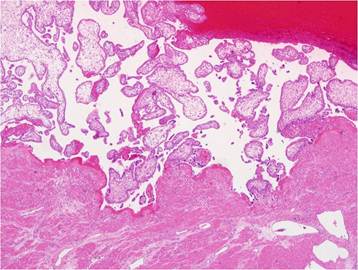

Figure 3

Chorionic villi in the myometrium of uterus, which explains the placenta percreta, are noted at microscopic field (x 40).

At the time of laparoscopy, 800 ml of fresh blood and 0.5-cm fundal defect of the uterus were noted (Fig. 2). The placenta and amniotic membrane were seen bulging spontaneously and slowly, and the uterine defect was gradually enlarging, with its size increased to 3 cm as last noted. Because the amount of blood in the ruptured area increased rapidly, we decided to convert laparoscopy to laparotomy. At the beginning of the laparotomy, the fetus was spontaneously delivered through the ruptured site. We preferred total abdominal hysterectomy to conservative management because of the large, fragile, and thin uterine wall with abundant blood vessels on the surface. The total estimated blood loss during the operation was 1000 ml; the patient was transfused 4 units of packed red blood cells and 2 units of fresh frozen plasma. Her recovery was uneventful, and she was discharged on postoperative day 6. The final pathological examination revealed that the chorionic villi had invaded the entire myometrium up to the serosa, confirming the diagnosis of placenta percreta (Fig. 3). The length of the fetus measured from the crown to rump was 9.0 cm, and fetal weight was 69.3 g; these measurements were consistent with 14 weeks of gestation.

Placenta percreta-induced uterine rupture in the first trimester in our patient may be attributed to the previous dilatation and curettage. Placenta percreta is the rarest form of placental abnormalities, with a 5-7% incidence among all placenta accreta cases [4]. In placenta percreta, the decidua basalis is partially or completely absent, and the chorionic villi invade the entire myometrium up to the serosa [5].